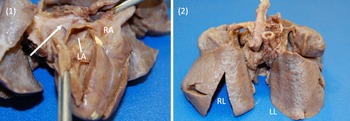

On arrival, the patient remained on an alprostadil infusion at 0.1 mcg/kg/minute, with oxygen saturations persistently in the 50’s despite ongoing respiratory support with nasal continuous positive airway pressure with FiO2 100%. The patient was immediately intubated but remained significantly desaturated. Repeat echocardiogram was obtained (Fig 1), which revealed the absence of pulmonary veins entering the atrium and absence of dilated pulmonary veins or large vertical vein. There was all right to left shunting across an unrestrictive atrial communication, and there was a large patent ductus arteriosus with predominantly right to left flow. A trivial pulmonary vein confluence was seen posterior to the left atrium. The right ventricle was dilated and the left ventricle was apex forming but appeared underfilled. Given that discrete pulmonary veins or venous drainage could not be delineated by echocardiography, cardiac CT scan was emergently obtained. Cardiac CT revealed a trivial pulmonary venous confluence with small left and right veins posterior to the left atrium; however, no discrete connection to the heart was identified (Fig 2). Due to the near atretic nature of this patient’s pulmonary veins and common pulmonary vein and lack of identified collaterals, extensive multidisciplinary discussions were held between Cardiology, Cardiac Intensive Care, Radiology, and Cardiothoracic Surgery teams. Ultimately, it was determined that there was no viable operative repair, and the decision was made between the family and the medical team to proceed with withdrawal of care. The patient was transferred back to the cardiothoracic ICU, compassionately extubated, and died shortly thereafter. An autopsy was performed which confirmed the absence of any pulmonary venous connection to the left atrium. There was a trivial pulmonary venous confluence superior to the left atrium as noted on the echocardiogram and CT, with a trivial vein that appeared to drain from the confluence to the innominate vein. No dilated pulmonary veins were demonstrated by autopsy. On gross examination, the lungs had a diffusely nodular appearance and histological examination revealed findings consistent with cystic lymphangiectasia.

Images 1, 2. Gross specimen images. (1) Posterior view. A trivial pulmonary venous confluence is seen superior to the left atrium (arrow). The left atrium has been reflected open and there is no identifiablepulmonary venous drainage entering the left atrium. The right atrium is notably dilated. (2) Anterior view. The lungs have a diffusely nodular appearance consistent with the post-mortem microscopic findings of cystic lymphangiectasia.